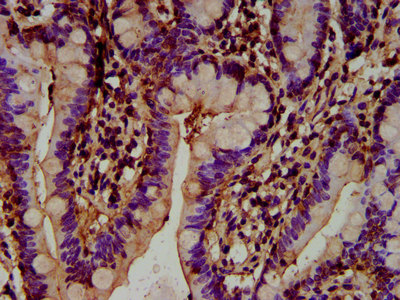

IHC image of CSB-PA732977LA01HU diluted at 1:300 and staining in paraffin-embedded human small intestine tissue performed on a Leica BondTM system. After dewaxing and hydration, antigen retrieval was mediated by high pressure in a citrate buffer (pH 6.0). Section was blocked with 10% normal goat serum 30min at RT. Then primary antibody (1% BSA) was incubated at 4°C overnight. The primary is detected by a biotinylated secondary antibody and visualized using an HRP conjugated SP system.